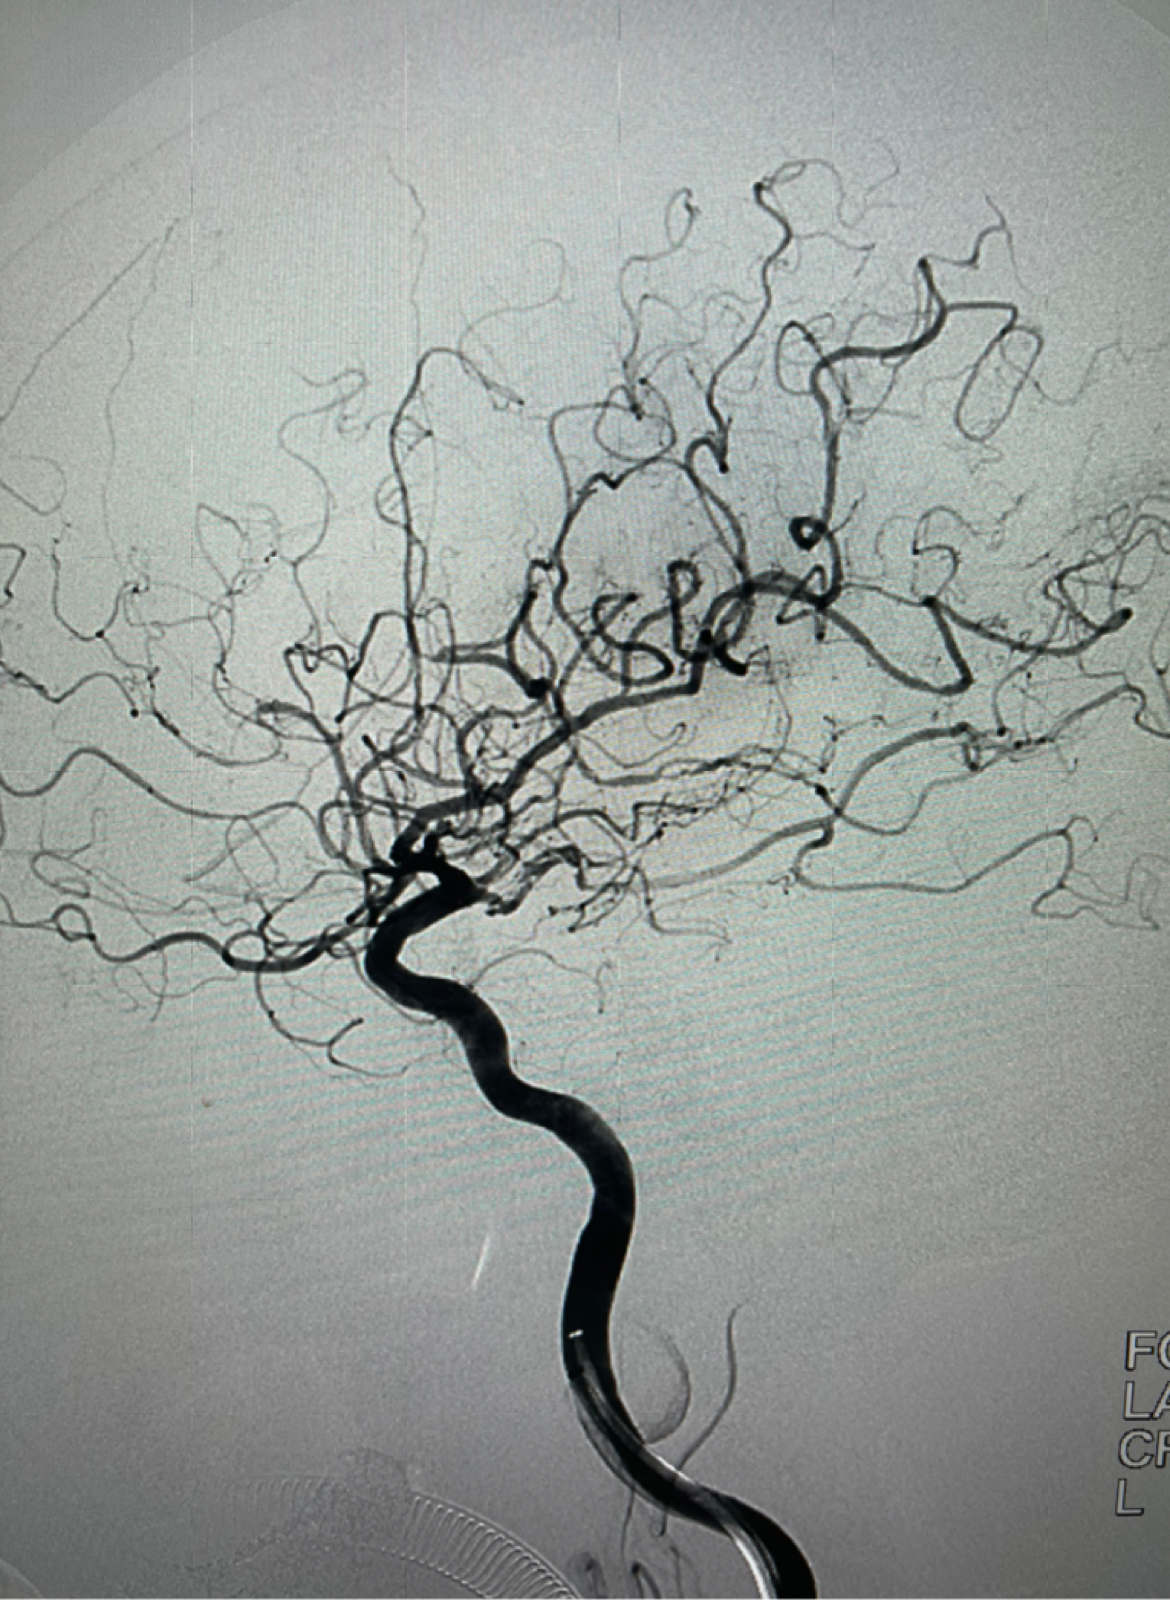

6F115c m中间导管到位后右侧工作位造影

微导丝携带2.0mmx15mmFastunnel输送型球囊扩张导管通过闭塞处造影位于血管真腔

2.0mmx15mmFastunnel输送型球囊扩张导管扩张后零交换扩张后植入TP EP2 4.0X23mm支架

支架打开良好

支架植入后正位造影提示大脑中动脉开通良好